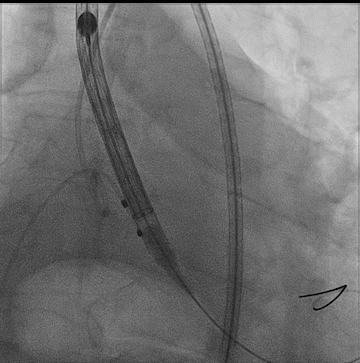

瓣膜定位

瓣膜完全释放形态良好,无瓣周漏